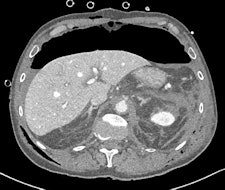

A full clinical evaluation of the patient is essential, and information about the etiology of the pseudoaneurysm, hemodynamic stability, and anticoagulation therapy is important. Studying the characteristics of the pseudoaneurysm is important, including anatomical localization, the size of the pseudoaneurysm sac, size of surrounding hematoma, diameter of pseudoaneurysm neck, vascular territory (superficial or deep/visceral) that the pseudoaneurysm arises from, and the type of end artery (expendable or inexpendable) in which the pseudoaneurysm is located. Ultrasound and CT angiography can determine all these features, although conventional angiography is used most of the time as a prelude to endoluminal treatment of the pseudoaneurysm, they stated.

radiopaedia.org/cases/gastroduodenal-artery-pseudoaneurysm.

A false aneurysm -- another term for a pseudoaneurysm -- is when there is a breach in the vessel wall such that blood leaks through the wall but is contained by the adventitia or surrounding perivascular soft tissue, according to Dr. Yuranga Weerakkody and Dr. Donna D'Souza et al, writing on radiopaedia.org. A direct communication of blood flow exists between the vessel lumen and the aneurysm lumen through the hole in the vessel wall. The risk of rupture is higher than that of a true aneurysm of comparable size due to poor support of the aneurysm wall, and thus false aneurysms generally require treatment.